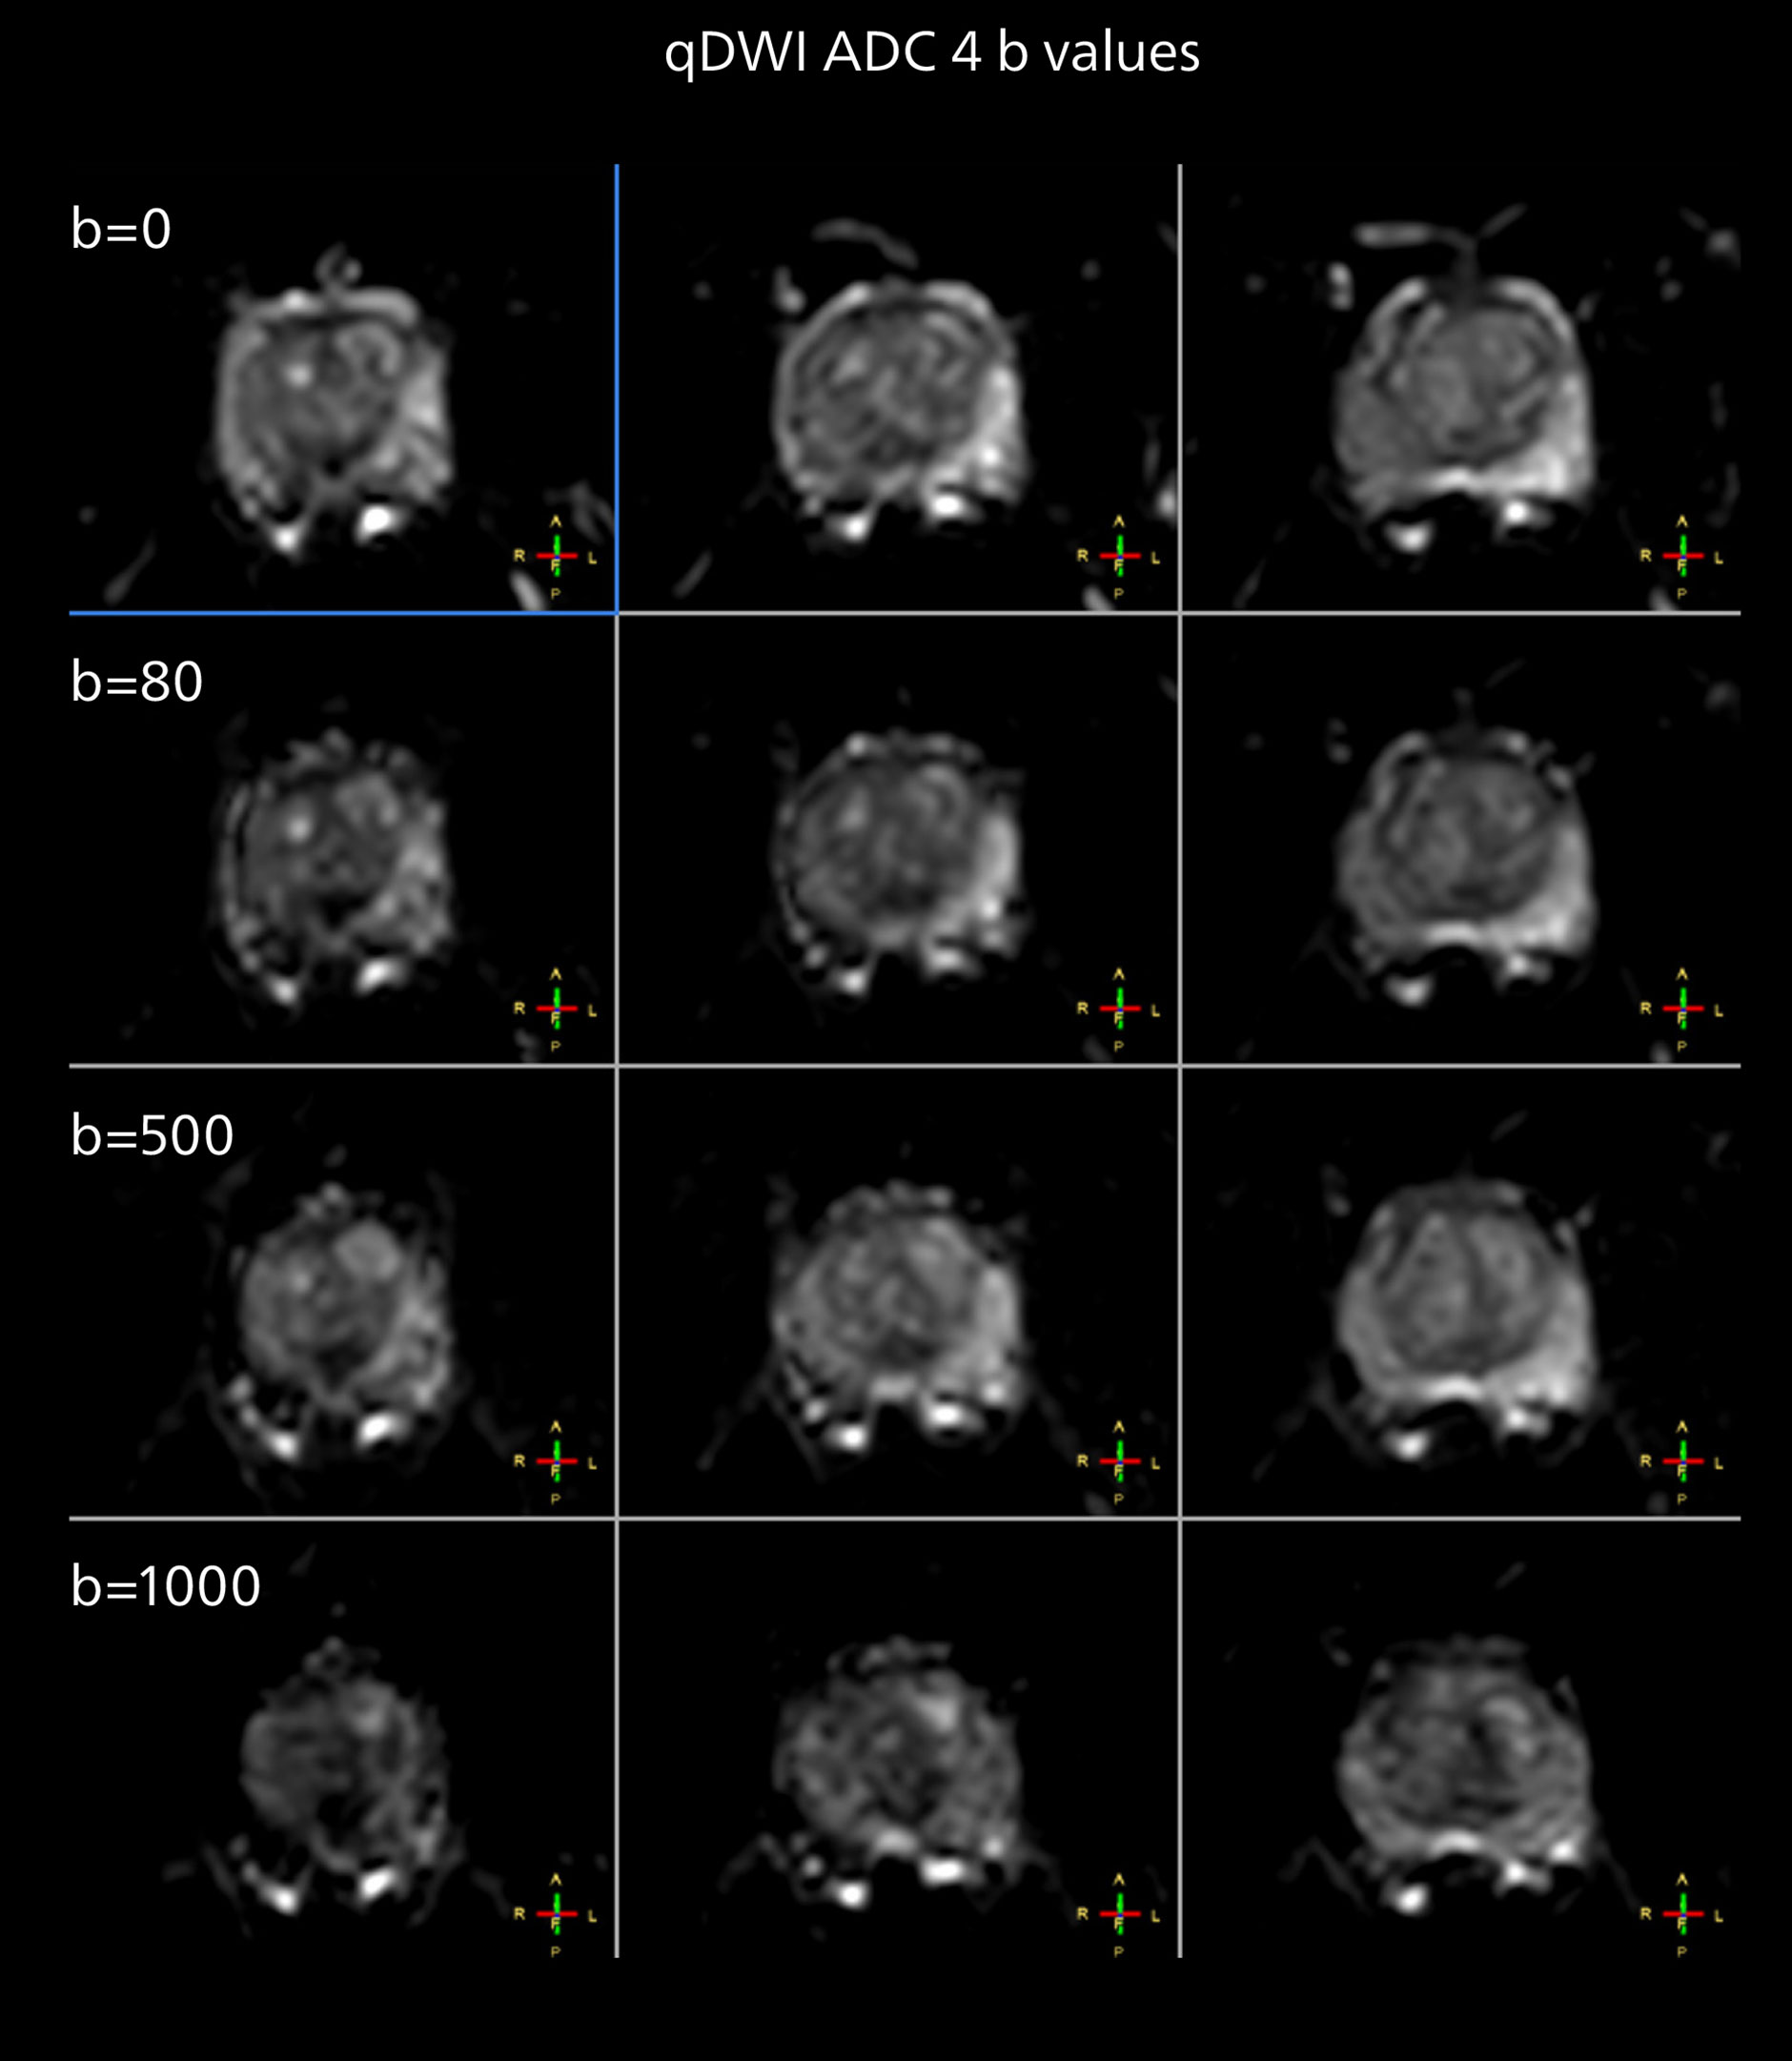

Diffusion weighted imaging of prostate

The examples on the left show the regular clinical diffusion protocol with four b-values up to b1000 s/mm². On the right, the T2W image shows a hypointense lesion that has low ADC and is clearly visible in b1400 and b2000 diffusion images, suggesting malignancy.

Diffusion weighted imaging of prostate

The examples on the left show the regular clinical diffusion protocol with four b-values up to b1000 s/mm². On the right, the T2W image shows a hypointense lesion that has low ADC and is clearly visible in b1400 and b2000 diffusion images, suggesting malignancy.